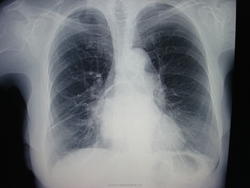

81 год, проходила проверочное исследование лёгких. Что может дать такую картину?

Половина желудка в средостении - газовый пузырь за сердцем. Тонкости - после контрастирования пищевода.

Такую картину, я думаю, может дать - 81 ГОД. А если серьезно, то я уже перестал отмечать эти грыжи при читке флюорограмм (а возможность диагностики их резко увеличилась при цифровой съемке), т.к. никто на них особо не обращает внимание, хирурги со скальпелями не бросаются. Да и пациентам, судя по всему, они не приносят особых неудобств. Эта немолодая леди, думаю, уже очень давно носит под сердцем желудок.